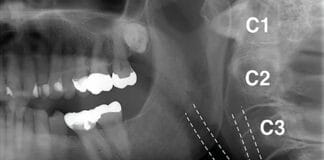

Panoramic and 3-Dimensional Images: Can They Detect Potential Carotid Artery Disease?